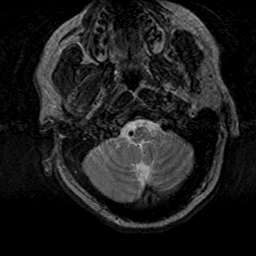

Subacute Stroke, overlay -- Slice #2

[Home][Help][Clinical] Slice 2